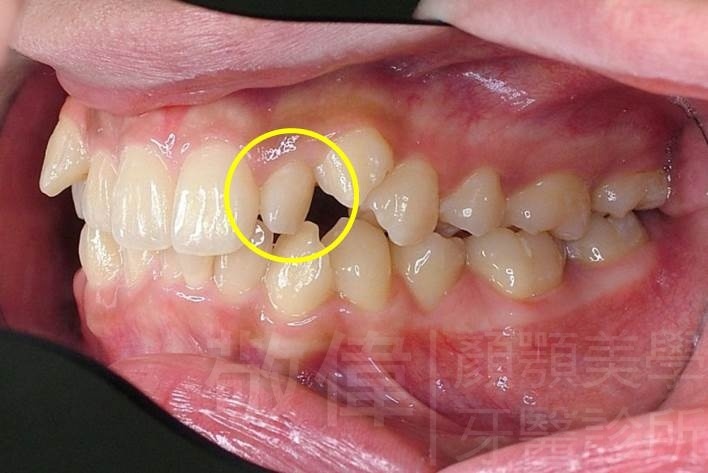

| 8 | 前牙美容 | 快速矯正之美容晶瓷貼片及晶鑽瓷冠 | ||